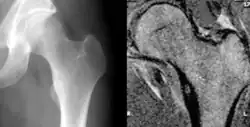

| Osteoid osteoma of the lesser trochanter: X-ray and MRI with marked sclerosis around the nidus | |

The most common symptom is pain that can be relieved with over the counter pain medication in the beginning. After the benign tumor develops further the pain can not be alleviated with medication and minor to severe swelling starts to occur. Although, in some cases the pain level remains the same for years, and regular NSAIDs intake keeps the pain at bay. The tumor is often found through x-ray imaging. Conventional radiographs reveal a well-demarcated lytic lesion (nidus) surrounded by a distinct zone of sclerosis that allow doctors to identify the tumor.[4]

Radiographs in osteoid osteoma typically show a round lucency, containing a dense sclerotic central nidus (the characteristic lesion in this kind of tumor) surrounded by sclerotic bone. The nidus is seldom larger than 1.5 cm.

The lesion can in most cases be detected on CT scan, bone scans and angiograms. Plain radiographs are not always diagnostic. MRI adds little to the CT findings which are useful for localisation. Radionuclide scanning shows intense uptake which is useful for localisation at surgery using a hand held detector, and for confirmation that the entire lesion has been removed.[8][9]